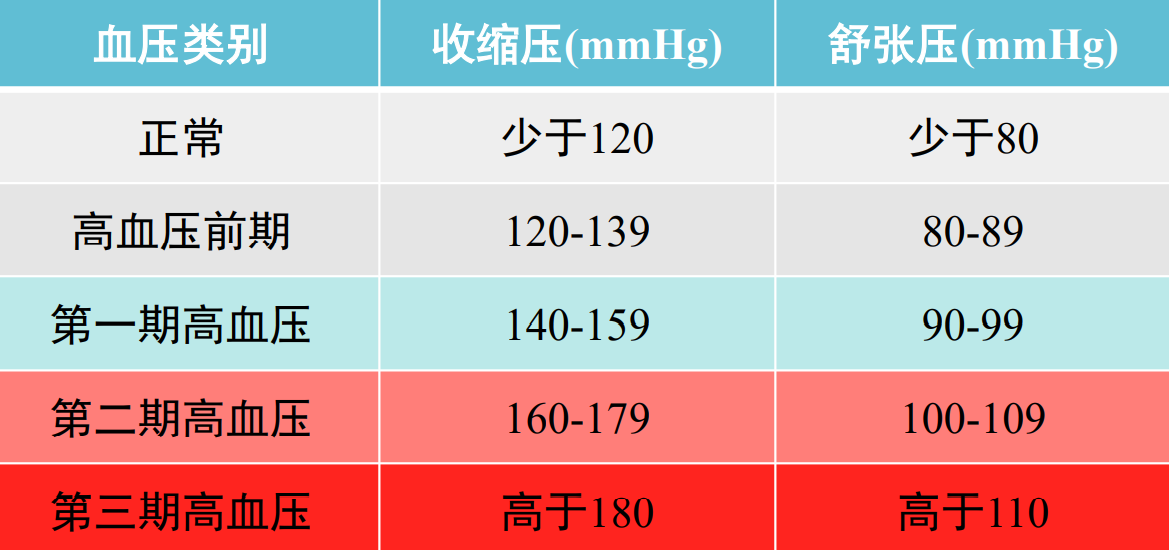

血压

血管内流动的血液对单位面积血管壁的侧压力,称为血压(blood pressure)

血压的正常值(考点):

收缩压(mmHg):少于 120;舒张压(mmHg):少于80.